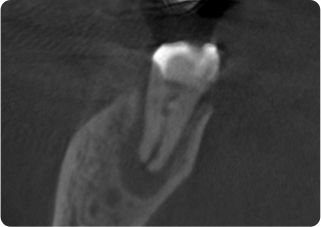

精密根管治療①

術前

術後

| 主訴 | 奥歯で噛むと痛い |

| 治療期間/回数 | 1ヵ月、3回 |

| 価格(税込) | 88,000円(税込) |

| リスク・副作用 | 病変再発、歯根破折の可能性 |

| ポイント | う蝕検知液を用い、むし歯の取り残しが無いようにし、ラバーダム防湿を行い、無菌的に根管治療を行った。根管充填材は、殺菌作用の強い保険適応外のMTAセメントを使用した。 |